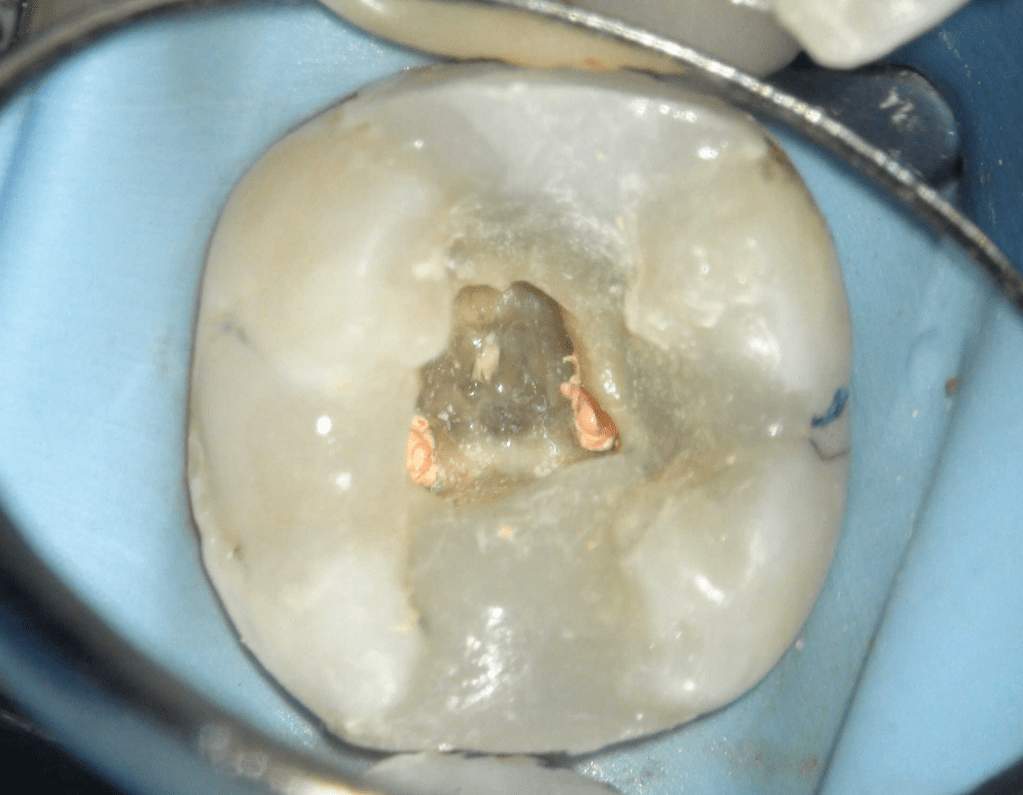

Reco pared vesticular